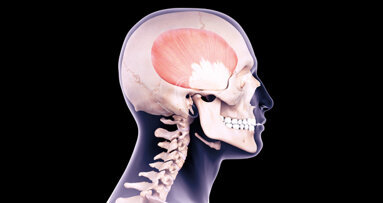

Nella sua forma tipica e maggiormente conosciuta, la celiachia si manifesta tra i 6 e i 18 mesi di età, dopo pochi mesi dall’introduzione del glutine nella dieta (con lo svezzamento), con una tipica sindrome da malassorbimento. Sintomi caratteristici sono la diarrea cronica con feci sfatte, voluminose e maleodoranti, il rallentamento della crescita, l’inappetenza, la distensione e il dolore addominale, l’ipotonia muscolare, l’irritabilità, la perdita di peso. La gran parte dei casi di celiachia, tuttavia, non è diagnosticata a causa di una sintomatologia atipica, prevalentemente extraintestinale: deficit staturale, osteoporosi, carenza di ferro, anemia, disfunzioni epatiche, aborti ricorrenti. Può essere associata a diabete mellito insulino-dipendente, tireopatie autoimmuni(1).